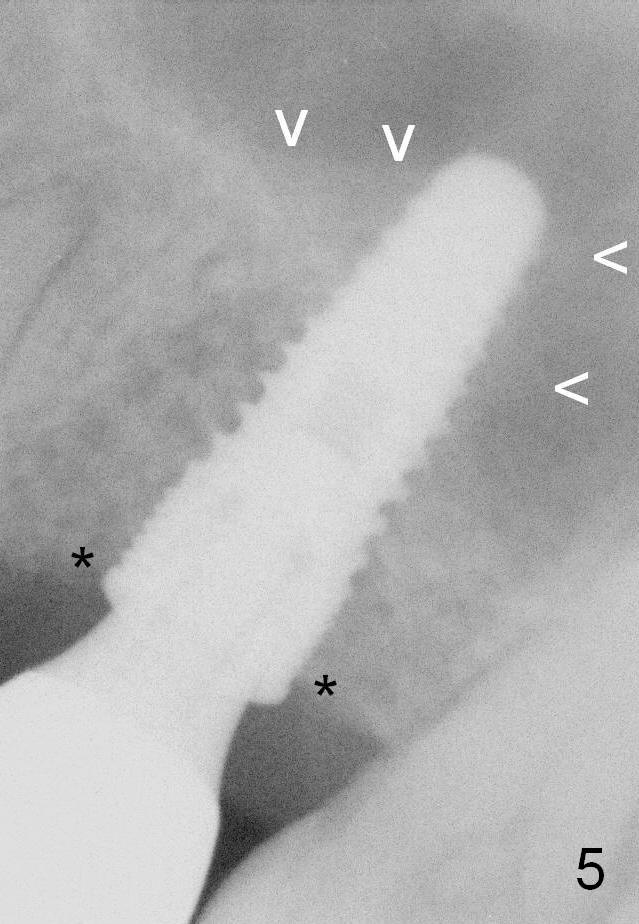

The patient returns for follow up 2.5 months post cementation. There is no crestal bone resorption (Fig.5 *), while the bone still surrounds the apex of the implant (arrowheads).